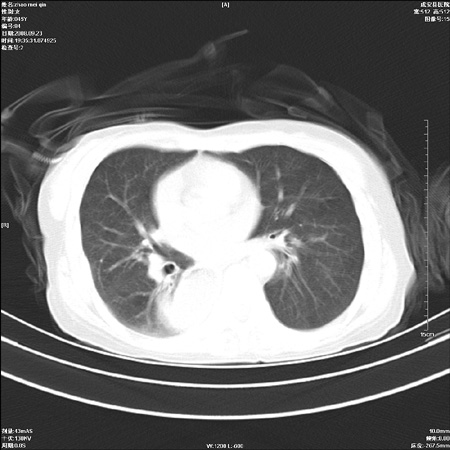

标题: CT15861:女 60 外伤后1小时 胸疼 [打印本页]

标题: CT15861:女 60 外伤后1小时 胸疼

外伤后1小时 胸疼 是外伤后引起的吗?

食道扩张明显下端逐渐变窄,倒像贲门失迟缓

食道ca术后胸腔胃,右肺挫伤?

非外伤性改变,典型的贲门失迟缓症

食道扩张明显下端逐渐变窄,大量食物存留,象贲门失迟缓症。